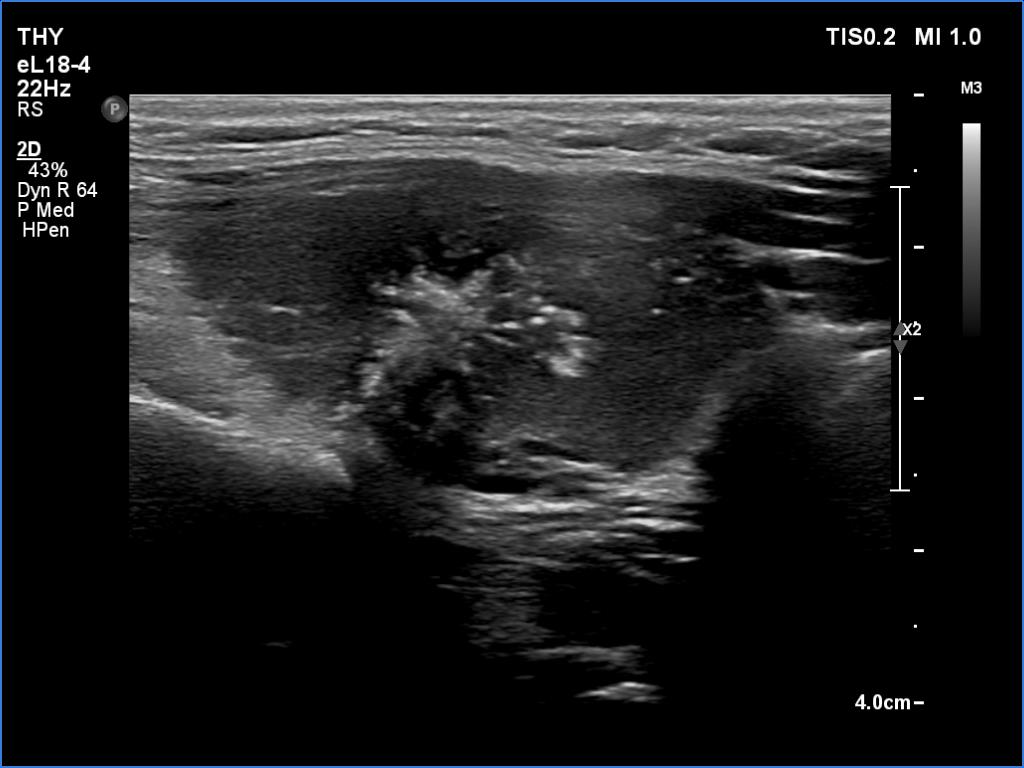

Ultrasonography. The thyroid was hypoechoic. The right lobe had a heterogeneous, dominantly minimally/moderately hypoechoic nodule in the ventrolateral part which had irregular borders and both perinodular and intranodular vascularity. There was another, hyperechoic star-like lesion in the central part of the right lobe. This lesion presented microcalcifications and was avascular. The left lobe was homogeneously hypoechoic.